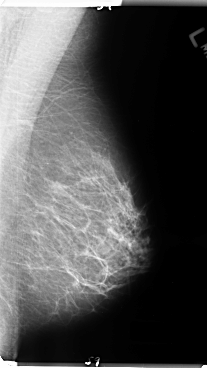

B_3146_1.LEFT_MLO

LEFT_MLO LINES 4776 PIXELS_PER_LINE 2688 BITS_PER_PIXEL 12 RESOLUTION 50 NON_OVERLAY